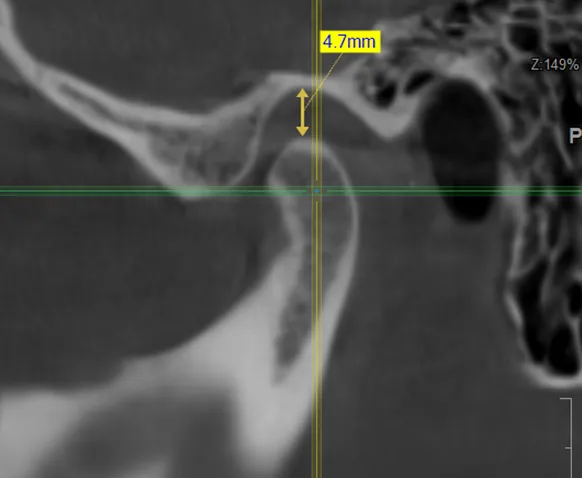

• компьютерная томография (КТ),